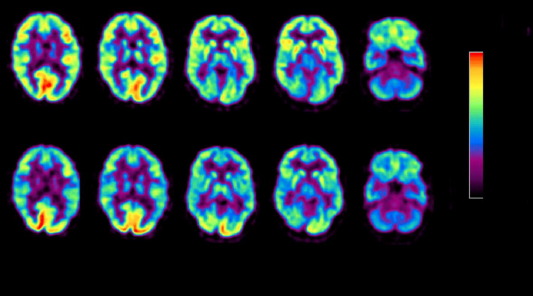

Нейробиология фудпорно. ![]() Наш мозг и система зрения тесно связаны между собой в вопросе добывания о оценки пищи. Есть мнение, что цветовое зрение человека развилось эволюционно как адаптация для определения ярких цветных спелых фруктов среди зелени. Научно доказано, что изображения пищи (картинки, заставки, видео, реклама, журналы и др.) очень сильно действует на нашу физиологию и активность мозга. Существуют обоснованные опасения, что растущее давление фудпорно может привести к плачевным последствиям. Научно доказано, что Passamonti and his colleagues (2009, p. 43) рассматривание изображений может вызвать голод и желание есть у полностью сытого здорового человека. Изменение активности мозга. Стимуляция дофаминовой системы вознаграждения. Одновременно активируются зрительная кора головного мозга и некоторые отделы префронтальной коры. Также значительно активируются отделы мозга, ответственные за вкусовое восприятие. Для нас важным является в первую очередь дофаминовая активация, которая связана с системой награды. Таким образом, все изображения еды, особенно гиперреалистиченые выступают как сверхнормальный дофаминовый стимул (изображения еды, кулинарные шоу, кулинарные книги). Сверхнормальный стимул. Давайте еще чуть-чуть теории, ок? Дальше будет легче, это важно для понимания. Итак, что такое сверхнормальный стимул? Научное определение: сверхнормальный стимул – это утрированная по одному или нескольким параметрам модель ключевого раздражителя, вызывающая какую-либо видоспецифическую реакцию типа «комплекса фиксированных действий» с большей степенью выраженности, чем исходно моделируемый стимул. Поясню. Так, когда мы сыты, мы не хотим есть. И это естественно. И даже если мы увидим обычную еду (капуста с горошком), нам ее есть не захочется. А вот фуд-порно – это другое дело. Фуд-порно – стимулирует мозговые центры сильнее, чем обычное изображение еды. Такая сильная стимуляция приводит к тому, что мы возбуждаемся и готовы есть, даже если не хотим. Вот «комплекс фиксированных действий» - это и есть поедание. Конечно, сверхнормальные стимулы этим не ограничиваются. Такие стимулы могут вызывать более сильную реакцию, чем естественные, и животные могут проявлять большее предпочтение к таким искусственным стимулам, чем к естественным. Пример сверхнормального стимула: кулик-сорока пытается насиживать гигантское яйцо, предпочитая его собственному яйцу. Или другой пример – высокие каблуки. Да, это вредно для ног и спины. И нормальная женская походка тоже привлекательна. Но на высоких каблуках бедра раскачиваются еще сильнее, и еще сильнее привлекают внимание. Поэтому высокие каблуки создают тоже сверхнормальный стимул. (High heels as supernormal stimuli: How wearing high heels affects judgements of female attractiveness, Evolution and Human Behavior, 34-3, 176-181) Особенно сильно дофаминовая система активируется при одновременной активации стимулов. Поэтому смешивая эротику и еду - можно совсем пожечь себе дофаминовые рецепторы)) ![]() Чем хуже дела - тем притягательнее картинки. С помощью МРТ ученые научились определять степень активации мозга на изображения еды у разных людей. Любопытно, что степень активации зависит от вашего веса и того, худеет ли человек. Люди с избыточным весом показывают намного более сильную активацию мозга в ответ на изображения еды, чем люди с нормальным весом. Более того, по уровню активации мозга в ответ на картинки можно даже предсказать, будет ли эффективна программа похудения даже через 9 месяцев! В целом изображение еды может усиливать общую активность мозга даже у здоровых добровольцев (in Wang et al.’s (2004)) до 24%. Вверху мозг после картинки с едой, внизу до. Красные оттенки показывают более высокую активность мозга, синие более низкую.